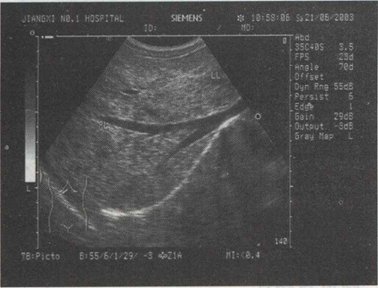

32.男,49岁,肥胖,血脂增高。结合超声声像图诊断为()